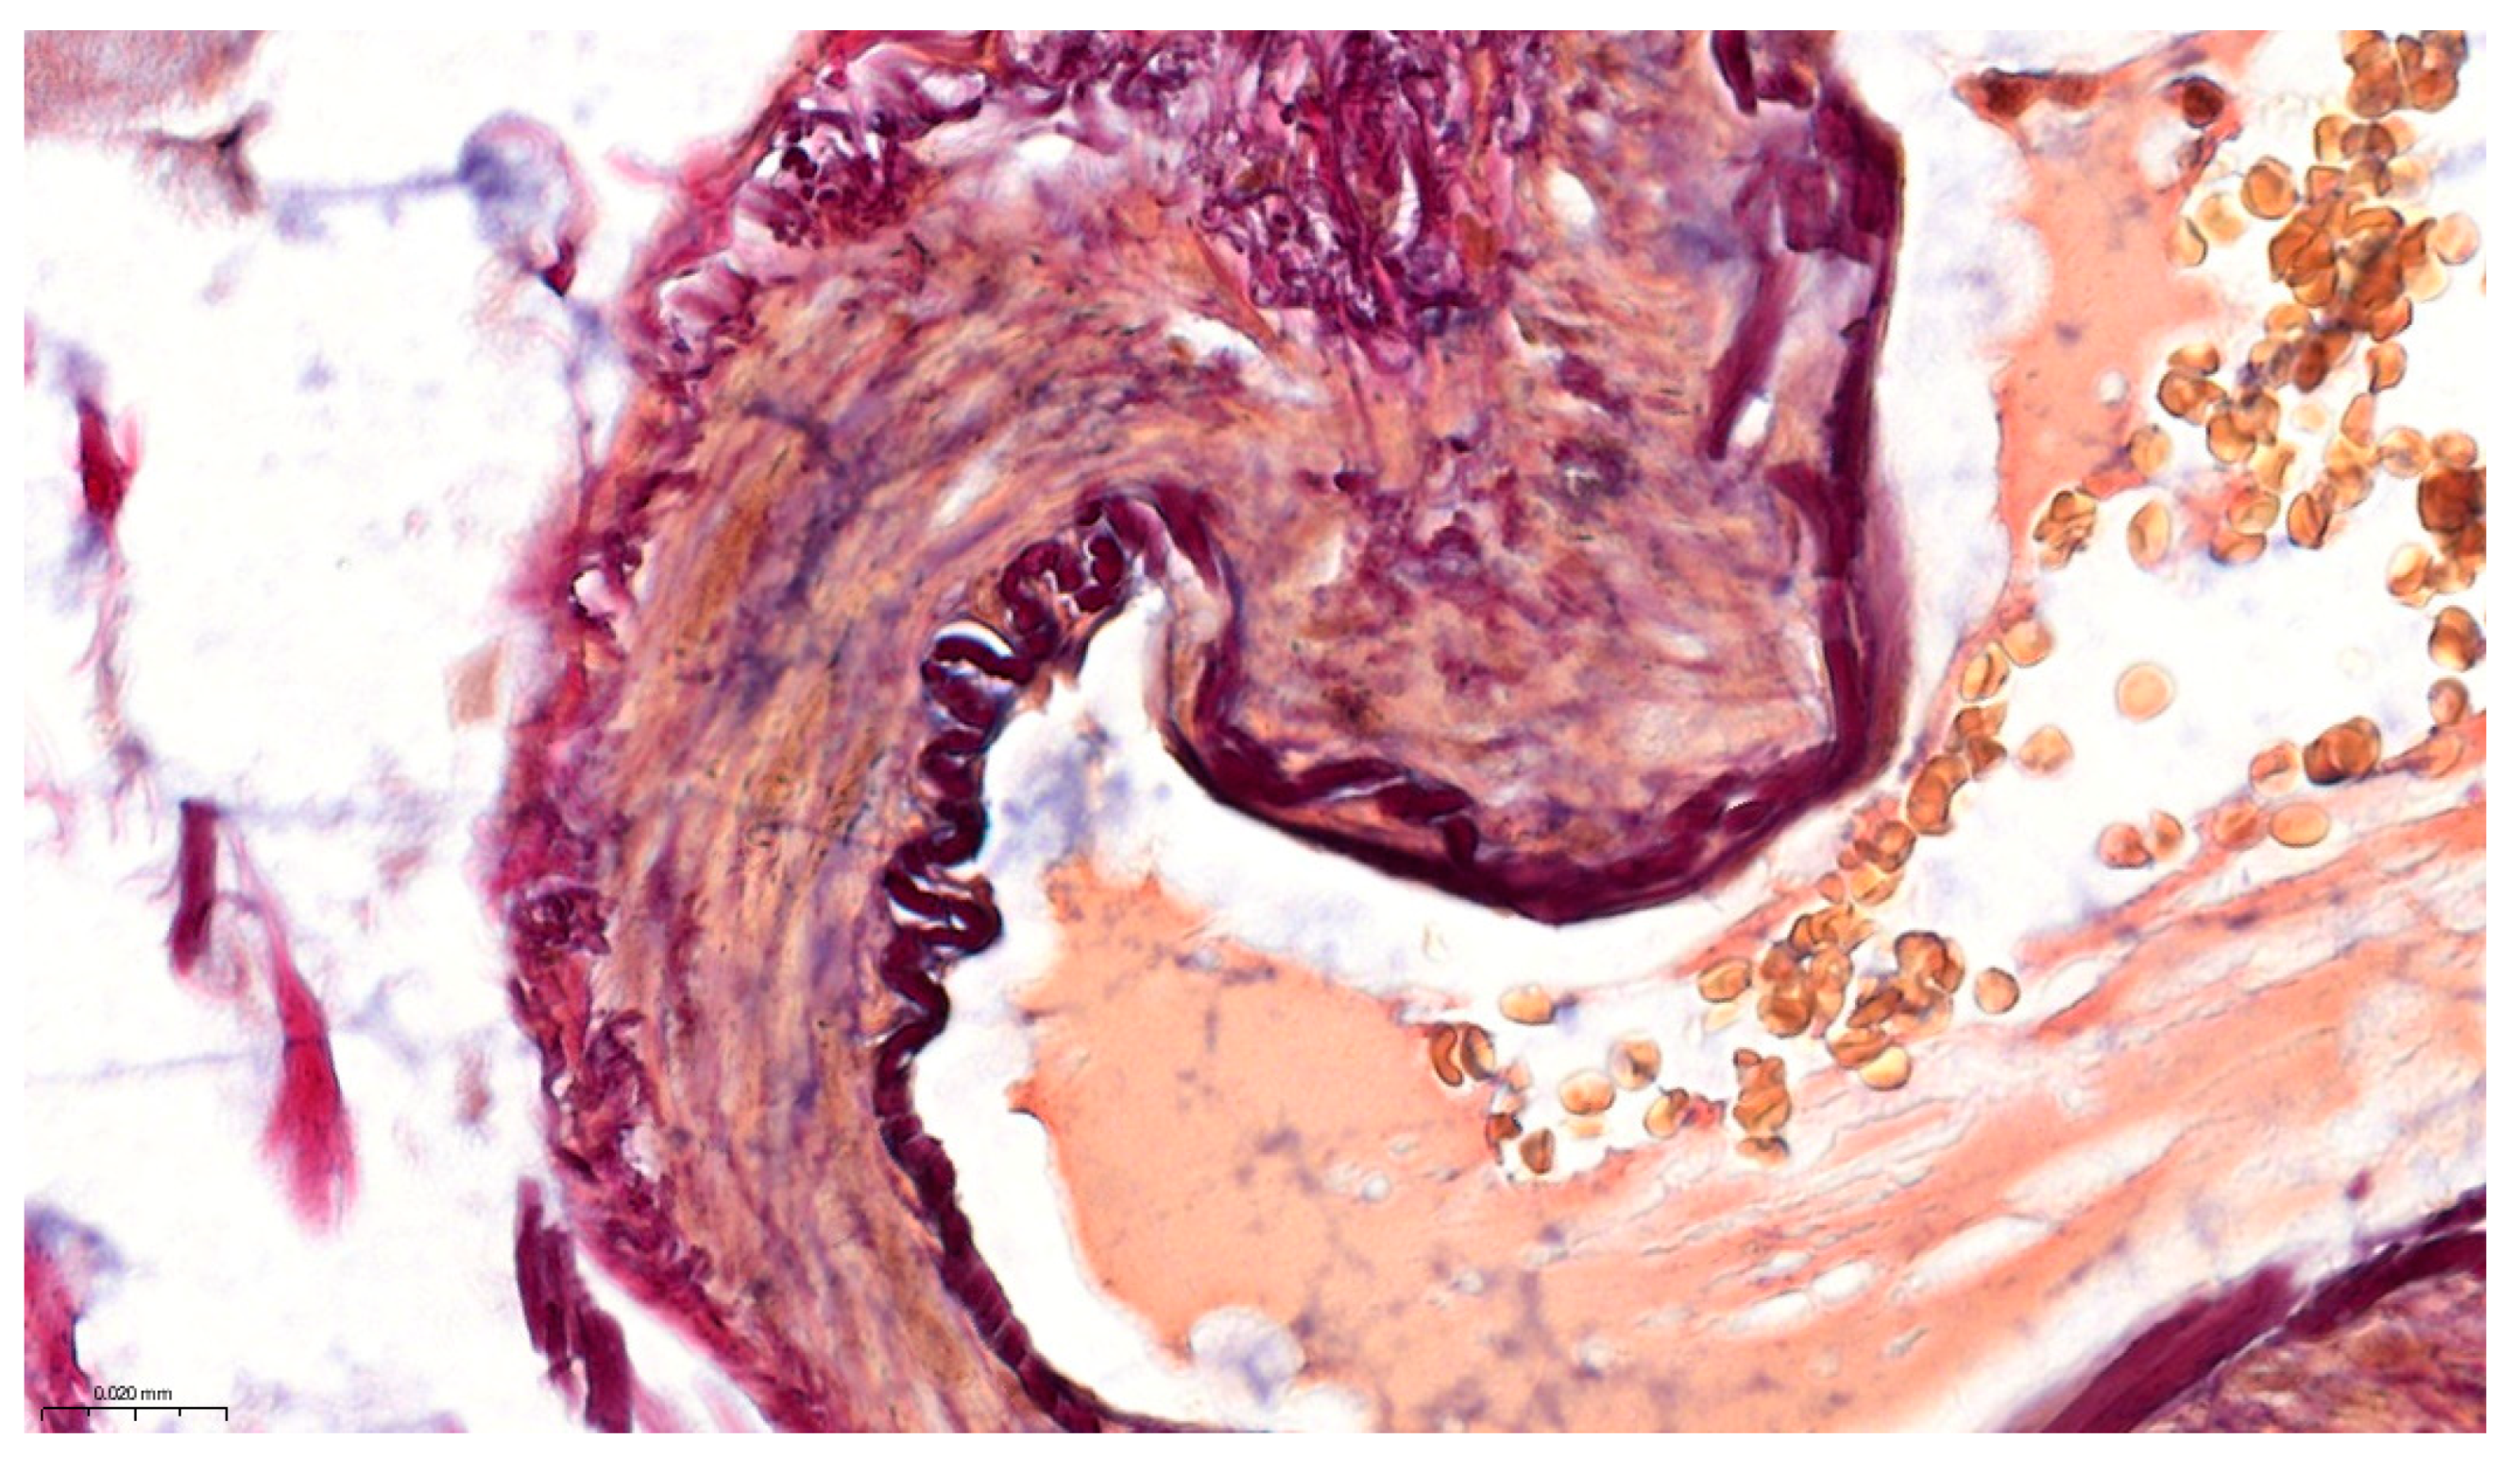

Figure 2 highlights the delicate lamina propria core of the villus, exemplifying the complete pallet of constitutive elements for loose connective tissue: capillary erythrocytes appear yellowish, the scarce collagenous matrix is stained bright red, and the more abundant fine elastic fibers are stained in a black–purple hue. The red coloration corresponds to acid fuchsin binding to collagen fibrils, while the black–purple elastic fibers reflect the uptake of Weigert’s resorcin–fuchsin. Scattered lymphocytes and other stromal cell nuclei were also tinted blue–black (with Mayer’s hematoxylin). This multicolor contrast allows individual tissue constituents to be distinguished at a glance—for example, an elastin fiber can be traced coursing between collagen bundles, and a thin muscle fascicle at the villus base is discernable by its yellow tone amid the red collagenous background (see Figure 3).

Pentachroma O-H proved particularly advantageous for visualizing vascular structures. Figure 4 focused on a detail of a small submucosal arteriole at 400×. The arterial wall’s architecture was vividly delineated: the concentric smooth muscle layers of the tunica media, encircling the lumen, were stained bright yellow, being neatly demarcated from the surrounding peripheral collagen in the outer tunica adventitia, which was stained red. At the interface between these layers, the internal elastic lamina became sharply visible as a thin black–purple band encircling the intima, thanks to the resorcin–fuchsin’s affinity for elastin. This level of detail—particularly visualizing the elastic lamina as a clear distinctly stained arterial wall structure—is rarely, if ever, achievable on a routine H&E sections, yet our Pentachroma O-H rendered it consistently, with remarkably high contrast. Erythrocytes within the arteriole lumen appeared in yellow–orange tones (picric acid staining of hemoglobin-rich cells), and the endothelial cell nuclei lining the vessel (tunica intima), as well as fibroblast nuclei in the vessel’s outer connective tissue, were clearly stained blue–black. These amounting details confirm that our original multicolor stain can concurrently highlight mucosal, stromal, and vascular components across different magnifications (Figure 3 and Figure 4), thus allowing for simultaneous assessment of vascular smooth muscle integrity (yellow media), elastic fiber distribution (purple–black lamina), and perivascular collagen (red adventitia), all in one view. Such detailed visualization can aid in evaluating pathological ileum changes like fibrosis or elastosis in vessels and stroma without relying on multiple separate stains.

Figure 2. Details of human ileum villus on longitudinal section, at high magnification (400×), in Pentachroma O-H staining: surface epithelium—absorptive enterocytes (Mayer’s hematoxylin stains basal nuclei blue–black, yet, at times, depending on sectioning, overlapping cytoplasmic reactivity may hinder visualization—more visible in the mucosa on the left side of the villus) and scattered goblet cells (Alcian Blue pH 2.5 stains acidic mucins turquoise–blue), sitting on a dark red-to-purple basement membrane (Van Gieson’s acid fuchsin stains collagen red, while Weigert’s resorcin–fuchsin stains elastic fibers dark purple) and a central stromal axis, with capillaries (picric acid stains the cytoplasm yellow–orange in erythrocytes), connective tissue fibers (scarce red collagen and more abundant dark purple elastin), and scattered mesenchymal/immune cellularity (blue–black nuclei). Scale bar—0.020 mm.

Figure 4. Vascular architecture details of the human ileum in Pentachroma O-H staining: high-power image (400×) of a small arteriole within the ileum submucosa. The wall of the vessel demonstrates concentric layers of smooth muscle in the tunica media stained yellow (picric acid), surrounded externally by red-stained collagen (acid fuchsin). The internal elastic lamina is distinctly visible as a sharply delineated black–purple band (resorcin-fuchsin), clearly separating the intimal layer from the muscular wall. The vessel lumen contains erythrocytes with a yellow–orange cytoplasm, while endothelial and stromal nuclei are blue–black. Scale bar—0.020 mm.